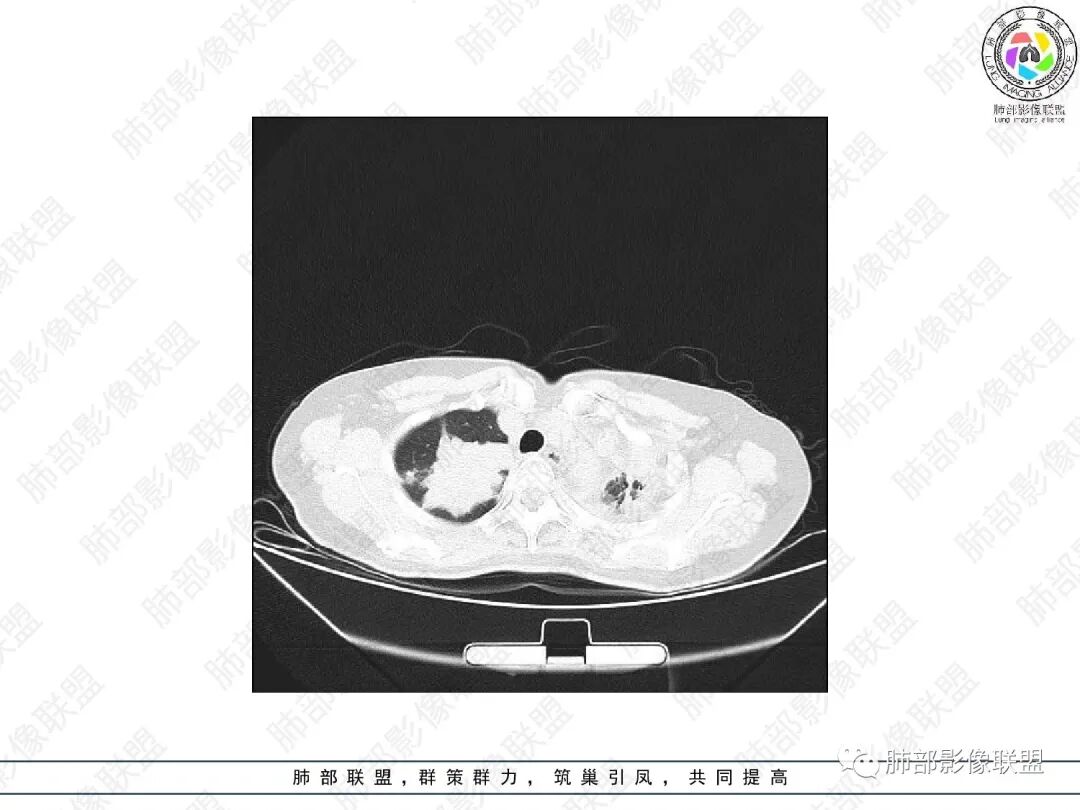

1.中年女性,主因“咳嗽、咳痰半年余”入院,既往史:8年前因左肺病在外院变行左肺叶切除术,诉术后抗结核治疗1年,具体病理等不详。实验室IGE显著增高。

2.胸部CT:右肺上叶及中叶不规则块状影,沿支气管走行方向指套样影,支气阻塞湖嵌塞,腔内可见高密度影。灶周可见磨玻璃,外围见结节影及树芽征。左肺体积缩小,见不规则条索影、胸膜增厚,纵隔牵拉左移。

3.综合分析:结合患者病史及胸部CT主要鉴别ABPA(右肺上叶不规则块影,指套样顺延支气管方向,抗结核治疗1年,肺部病灶仍明显)及继发性肺结核TB(右肺上叶不规则肿块,其可见高密影,边缘模糊,周围卫星灶、树芽征,沿支气管爬行)。

完善气管镜及病理、检验结果(IgE显著增高)等支持ABPA诊断。且给予激素及伊曲康唑治疗后复查胸部CT提示病灶较前吸收,所以诊断明确。